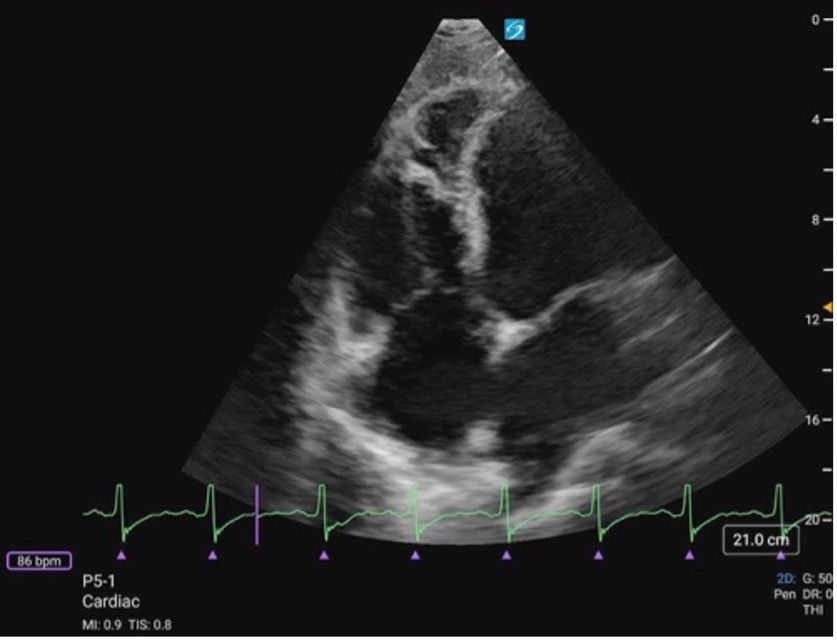

Apical Four Chamber

In A4C view, you can assess LV wall motion at the basal, mid, and apical levels of the inferoseptal and anterolateral walls (figure 19). This view is also useful for visual estimation of overall contractility and evaluation of the LV’s size and shape throughout systole and diastole.

It is important to avoid foreshortening in the A4C view, as this can underestimate LV length and overestimate function. If the LV appears round or blunt at the apex, the image is likely foreshortened—slide the probe laterally and slightly inferiorly to better align with the cardiac apex, and angle it more anteriorly (toward the face) to bring the true apex into view and ensure a full-length chamber.

Formal echocardiography uses apical views to calculate EF using Simpson’s biplane methods; however, this is beyond the scope of PoCUS practice